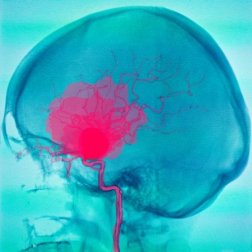

A dura-máter e a aracnoide são duas das três meninges presentes no ser humano. As meninges são as estruturas que envolvem o sistema nervoso central. Uma hemorragia subdural ou subaracnóidea se refere a uma hemorragia que ocorre abaixo de cada uma dessas duas meninges.

Em uma hemorragia subdural ou subaracnóidea, a primeira circunstância é a saída de sangue dos vasos sanguíneos, que fica armazenado nos espaços entre as meninges. Isso causa danos no tecido encefálico, gerando, assim, diversos quadros clínicos.

A hemorragia subaracnóidea é definida como o acúmulo de sangue entre a aracnoide e a pia-máter. O sangue costuma ser de origem arterial e pode corresponder a diversas causas. A mais frequente é a ruptura de um aneurisma, mas também pode ser causada por malformações vasculares.